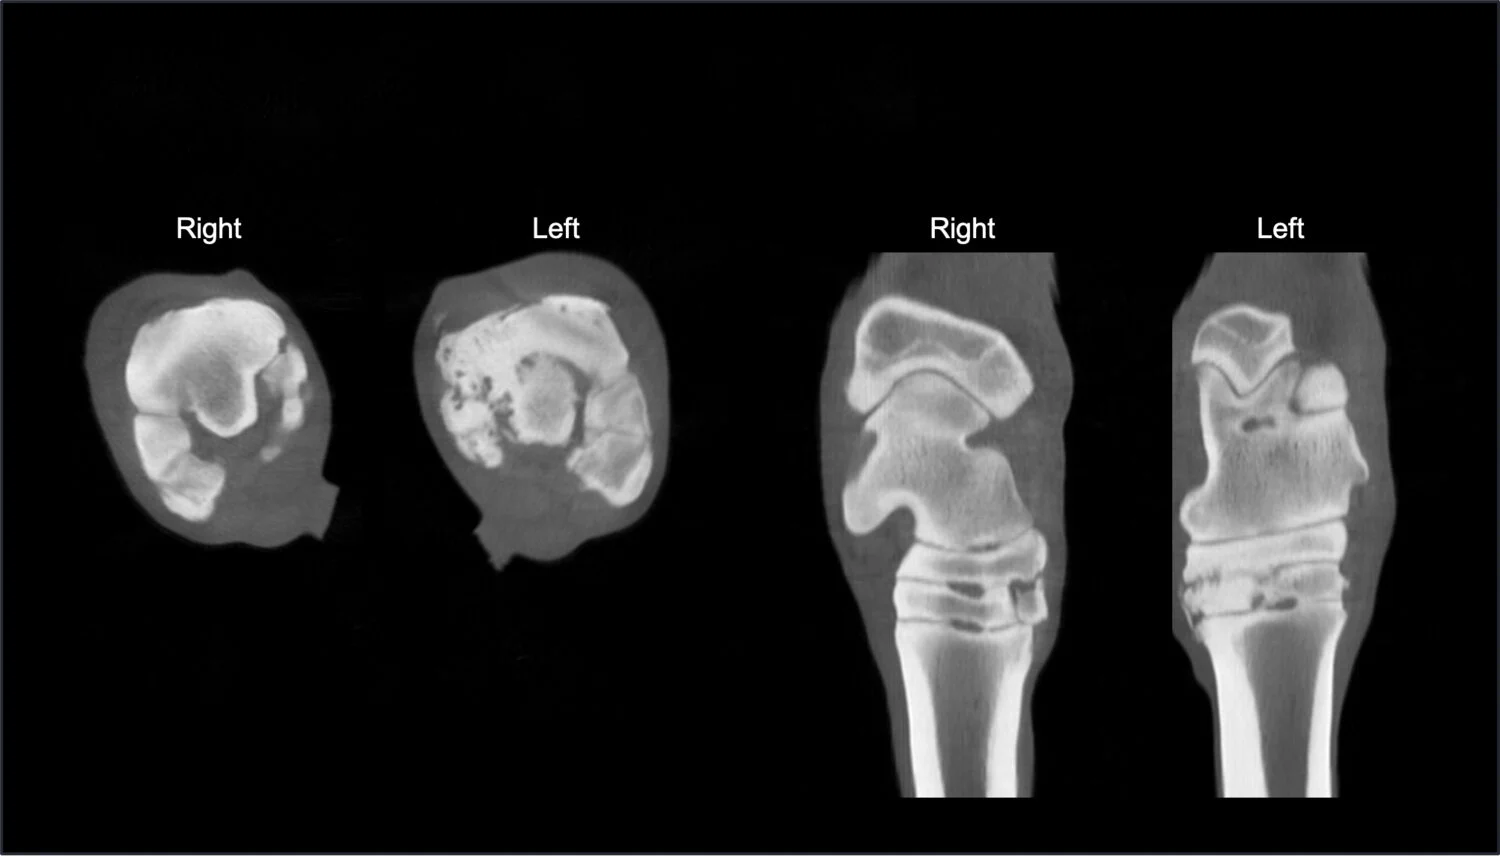

• Standing CT Is a superb tool for diagnosing lameness problems in limbs. It is also best-in-class for diagnosing diseases of the head, such as ethmoid hematoma, sinus problems and teeth/jaw problems; and for diagnosis of equine neck diseases, such as osteoarthritis and fractures.

• Lameness and musculoskeletal issues are common in horses and can be hard to diagnose. Because of the high quality of Equina images, it is particularly helpful in finding the specific causes of lameness and other lower limb problems.

• For Thoroughbred owners, who are heavily invested in their horses for racing and breeding, Equina can preserve the quality of life and financial value of racehorses through incorporation into several parts of routine practice. This includes: pre-purchase images of Yearlings; pre-race monitoring for stress fractures in active racehorses; and CT monitoring during training to identify early signs of stress fracture to enable smarter training.

• Standing CT is better than other imaging modalities because of the combination of the ease of image acquisition and the quality of the images. In about 30 minutes, your vet can have a comprehensive assessment of the lower limbs, or head and neck of your horse without the risk of general anesthesia. With this detailed information, veterinarians can develop more personalized and effective treatment plans for your horse, leading to quicker recovery and a higher chance of returning to training and performing.